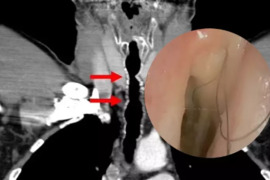

Nadir görülən xəstəlik: Boğazında durmadan uzanan tüklər həkimləri təəccübləndirdi

Uzun illər siqaret çəkən kişi boğazının arxasında qara, ipli tüklər çıxmağa başlayıb. xarici mediaya sitinadən xəbər verir ki, həmin şəxs boğazında durmadan uzanan tüklər onu qorxudmağa başlayıb. 52 yaşlı kişi həkimə müraciət edib. Bu qəribə hall həkimləridə təəccübləndirib. Həkimlər bildiriblər ki